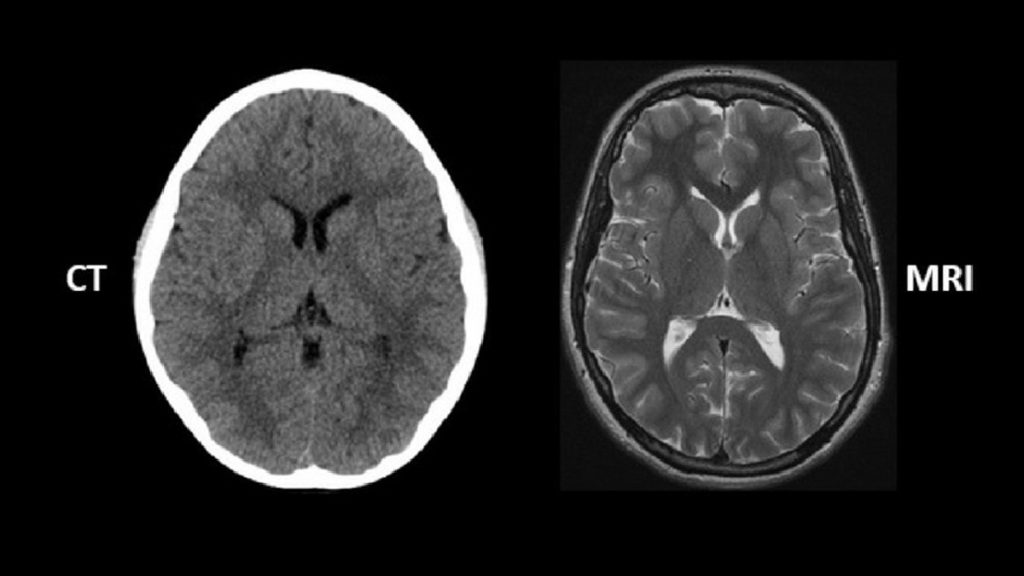

مقایسه مزایا و خطرات ام آر آی و سی تی اسکن

ام آر آی و سی تی اسکن دو روش تصویربرداری پزشکی هستند که برای تشخیص بیماریها و آسیبها استفاده میشوند. هر کدام از این روشها مزایا و خطرات خاص خود را دارند. در جدول زیر، مقایسهای بین این دو روش انجام شده است:

MRI به طور معمول در تشخیص ضایعات مغزی کوچک، دقت بیشتری نسبت به سیتیاسکن نشان میدهد.. CT معمولاً در مشاهده مناطق کوچک خونریزی بهتر است.